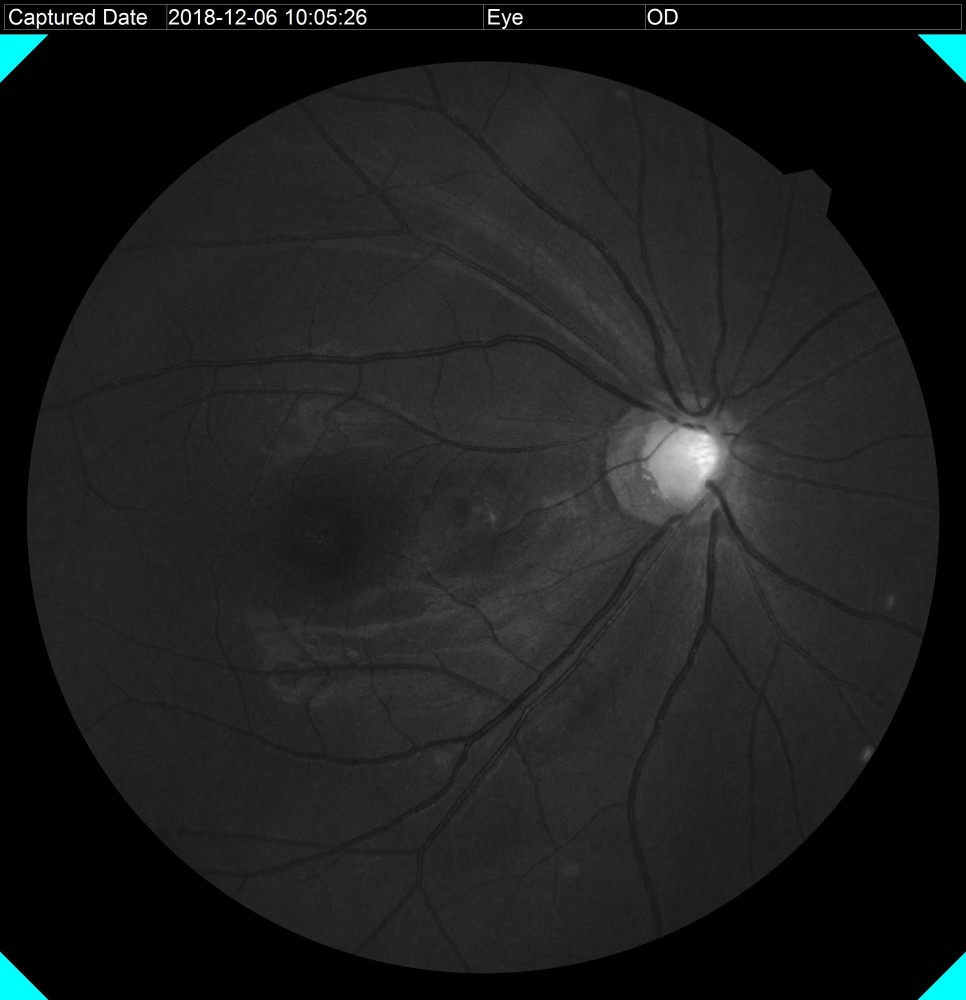

안저검사와 안구광학 단층촬영이 가능한 RS330과 OPTOS

안저 검사는 동공을 크게 하지 않고도 눈 속을 들여다 볼 수 있는 장비입니다.본원에는 안저의 중심부(30도)를 볼 수 있는 RS330과 중심+주변부(200도)까지 확인 가능한 OPTOS가 있습니다.

안저검사를 통하여 시신경의 형태, 시신경유두의 함몰비, 시신경 손상 여부 등을 확인할 수 있습니다.

녹내장 환자의 안저사진 안저검사를 통하여 녹내장 유무가 확인되면 안구광학단층촬영(OCT)을 통하여 시신경의 손상 정도를 보다 정확하게 확인합니다.